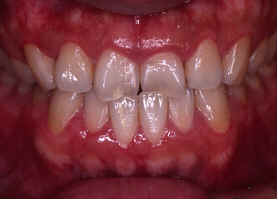

【治療前】

前歯の反対咬合が

認められます。